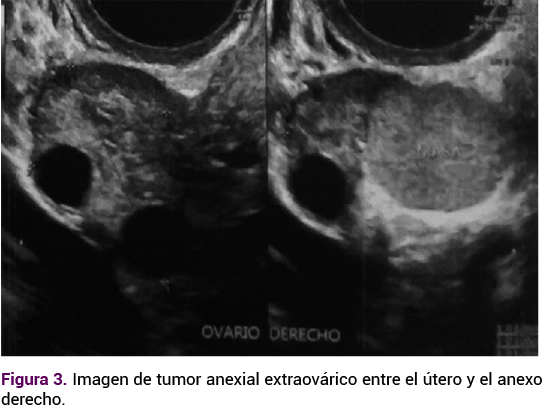

En el ultrasonido endovaginal el útero se encontró aumentado de tamaño debido a la miomatosis uterina intramural y subserosa de medianos elementos, con imagen isoecoica, extraovárica, de 26 x 20 x 18 mm, en la región anexial derecha entre el útero y el ovario ipsilateral, que a la aplicación de Doppler mostró aumento de la vascularidad.

<strong>Figura 3</strong>

Figura 3. Imagen de tumor anexial extraovárico entre el útero y el anexo derecho.